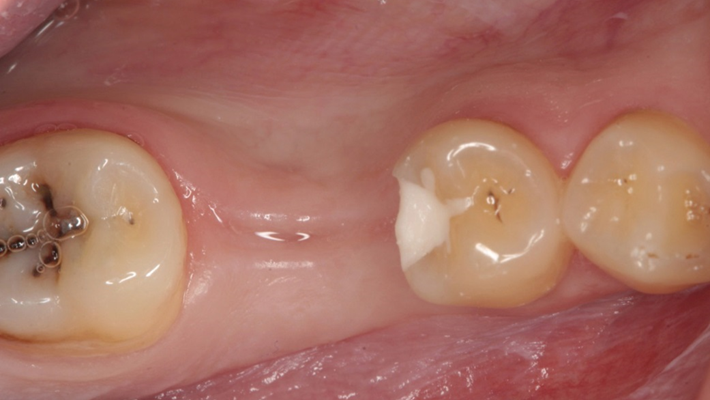

Clinical case: Ridge splitting technique using SmarThor + AnyRidge as expander

- Courtesy of Dr.Kwang-Bum Park, Korea -

AnyRidge, ridge splitting, GBR, Dr. Kwang-Bum Park, mandibular posterior, SmartThor, Mega-Oss, thin ridge, bone regeneration